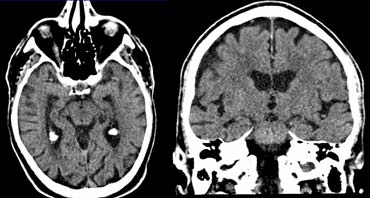

CT with negative scan angle for optimal vizualisation of the hippocampus in the transverse plane CT with negative scan angle for optimal vizualisation of the hippocampus in the transverse plane

CT protocol

CT can be useful when contraindications prevent MRI or when the only reason for imaging is to rule out surgically treatable causes of cognitive decline.

In the transverse plane the scan angle should be parallel to the long axis of the temporal lobe.

Use of multi-detector CT will enable coronally reformatted images to be reconstructed perpendicular to the long axis of the temporal lobe for optimal vizualisation of the hippocampus.